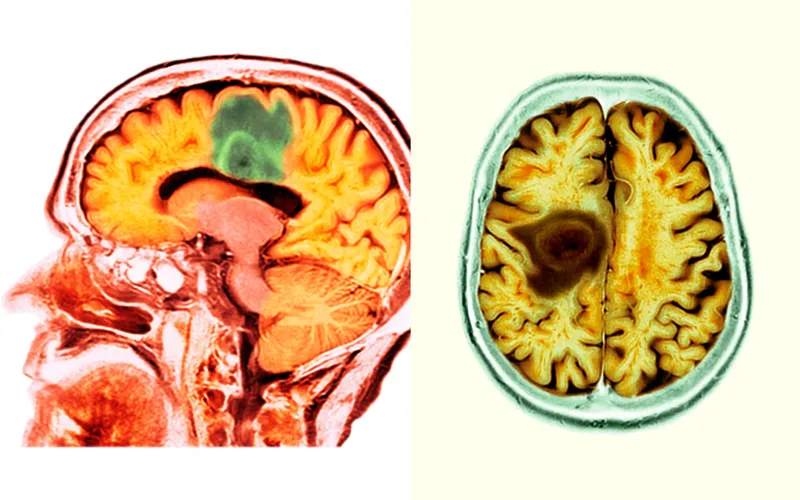

Când am fost diagnosticat pentru prima dată, mi s-a dat un pronostic de puțin mai mult de un an de trăit. După ce RMN-ul post-radiație a arătat că cancerul meu nu avansase, am simțit că pot respira pentru prima dată după luni de zile. Știam că cancerul mă va ucide la 50 de ani, dar am început să cred că aș putea trăi cel puțin câteva luni în plus. Am tricotat o eșarfă de culoare crem pentru mama mea, care a durat aproximativ o săptămână de tricotat, iar apoi un șal colorat pentru Hannah, care a durat ceva mai mult.